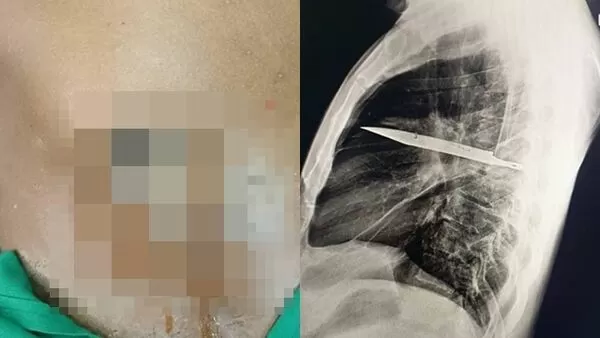

▲男子照X光才發現胸腔內有一把刀。(圖/翻攝academic.oup.com,下同。)

坦尚尼亞發生罕見病例,一名44歲男子右側乳頭附近持續流出惡臭膿液,嚇得趕緊就醫。他接受X光檢查才發現,胸腔內竟藏有一把刀子,估計已經長達8年之久。此病例研究被發表在《外科病例報告期刊》(JSCR)。

未料,X光檢測結果令醫師大感震驚,因為畫面清楚顯示,患者胸腔內有一個利刃狀的「金屬殘留物體」,從肩胛骨穿入,周圍被膿液和壞死組織包圍。